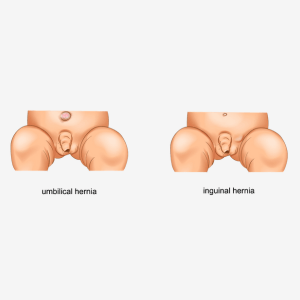

Hernias